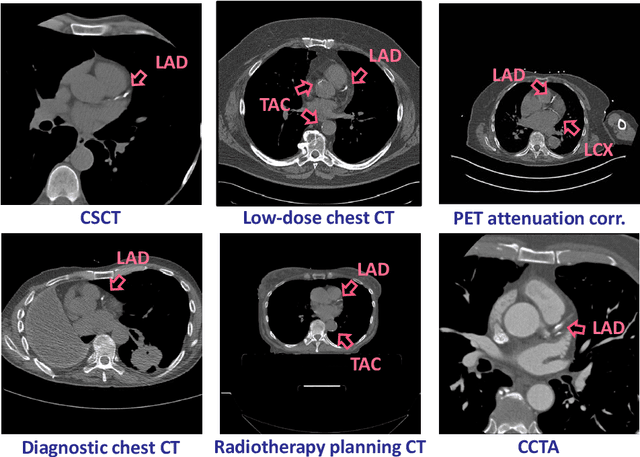

Calcium scoring, a process in which arterial calcifications are detected and quantified in CT, is valuable in estimating the risk of cardiovascular disease events. Especially when used to quantify the extent of calcification in the coronary arteries, it is a strong and independent predictor of coronary heart disease events. Advances in artificial intelligence (AI)-based image analysis have produced a multitude of automatic calcium scoring methods. While most early methods closely follow standard calcium scoring accepted in clinic, recent approaches extend this procedure to enable faster or more reproducible calcium scoring. This chapter provides an introduction to AI for calcium scoring, and an overview of the developed methods and their applications. We conclude with a discussion on AI methods in calcium scoring and propose potential directions for future research.